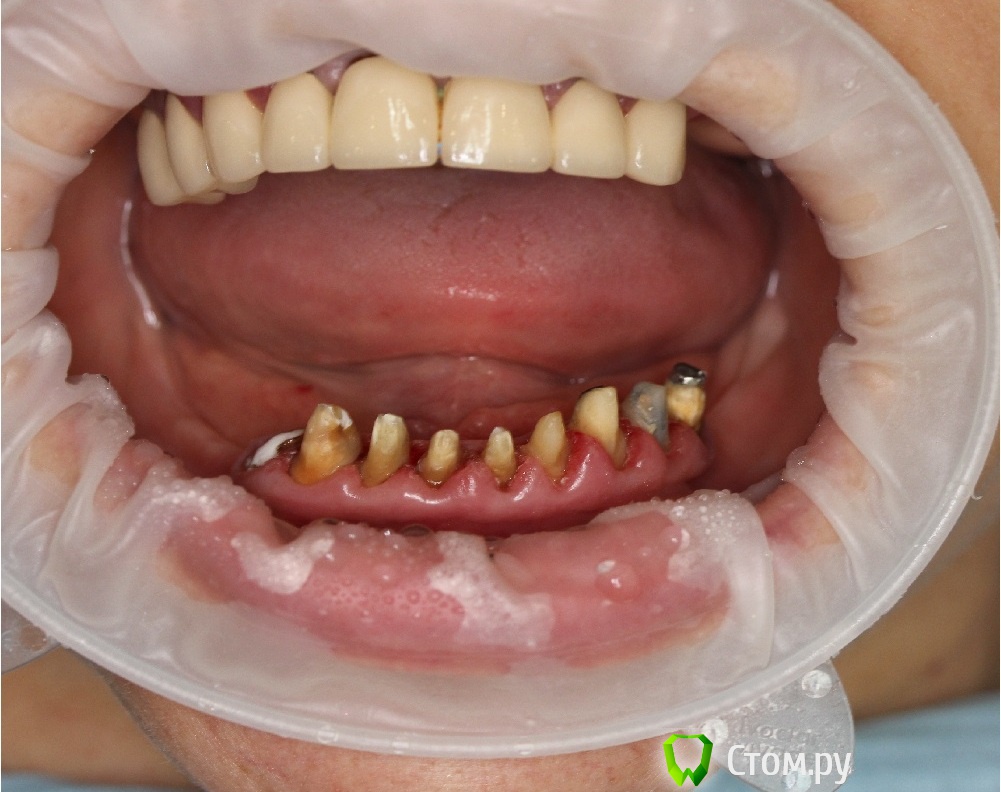

Dr.Sham Опубликовано 14 октября, 2014 Поделиться Опубликовано 14 октября, 2014 (изменено) Планируется удаление всех зубов на НЧ. Пациентка хочет несъемную конструкцию.Вот нарезка.Планируется имплантация Ankylos в позициях 46, 44, 42, 32, 34, 36.В боковых отделах дефицит всего.Думаю удалить зубы через один, чтобы на них временная конструкция держалась, а в промежутках имплантаты.В переднем отделе узко, либо узкие ФДМки, либо заглушка и в овоид край времянок или закрыть свободным трансплантатом.Что думаете?В боковых отделах вопрос...короткие имплантаты и НКР? От сложной костной пластики пациентка отказывается категирочески. Сверху пациентка так же хочет несъем. Поэтому все на 4-х, наверное, не самамя удачная конструкция здесь. Зубы сохранить никак, преп под десной местами по 3 мм. ну и дентин весь мягкий. Изменено 14 октября, 2014 пользователем Dr.Sham Ссылка на комментарий